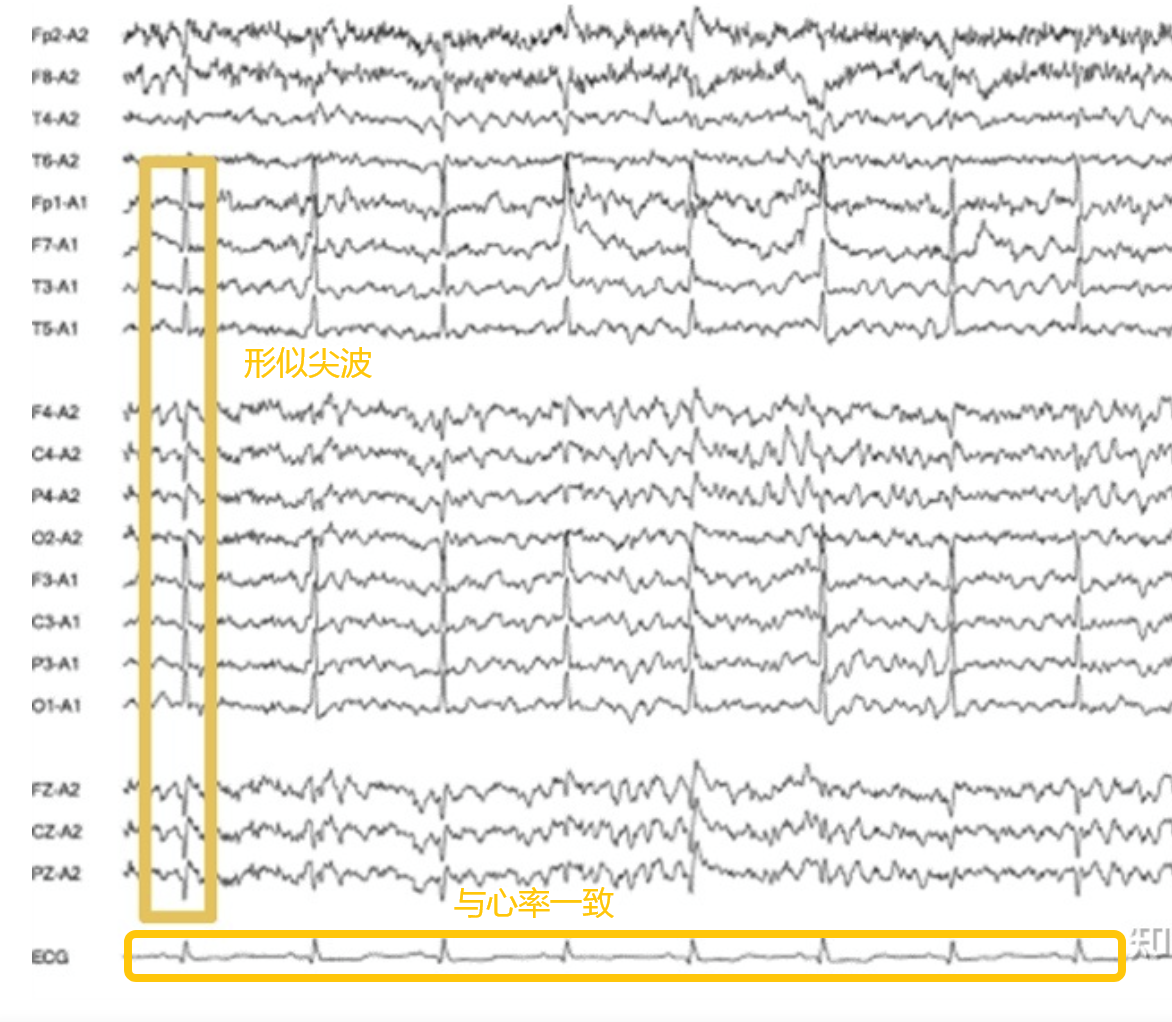

3. 心电伪迹

心电伪迹 是指由于心脏电活动(ECG)在脑电或其他体表电极上引入的信号干扰。

来源:心脏本身的电活动

频率:与心率一致,一般 1–2 Hz

振幅:中等,约 20–100 μV,比正常脑电高

波形:类似 QRS 波,尖锐而规律,有明显周期性